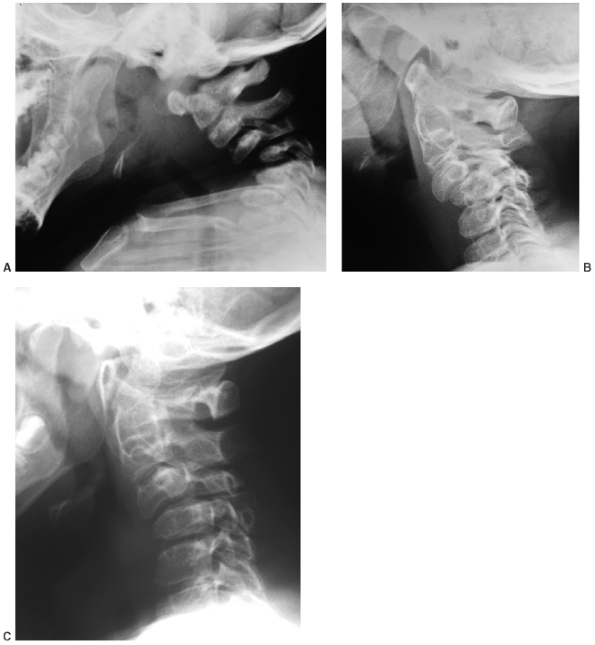

Cervical kyphosis is seen in one third to one half of patients (8,91);

this disorder may be present in infancy, and its course is variable.

Spontaneous resolution has been reported in a number of patients, even

in those with curves of up to 80 degrees (92,93) (Fig. 8.16 A, B). However, other cases progress, and there are several reports of quadriparesis resulting from this deformity (8,94). Scoliosis develops in at least one third of patients (91),

Figure 8.16 Cervical kyphosis in a 1-year-old child (A)

with diastrophic dysplasia is pronounced, with marked deformity of C4. The findings of neurologic examination are normal. Four years later, the condition is markedly improved without any intervention (B), and 7 years later the vertebral bodies have been restored to nearly normal shape, although the canal remains narrow (C). |